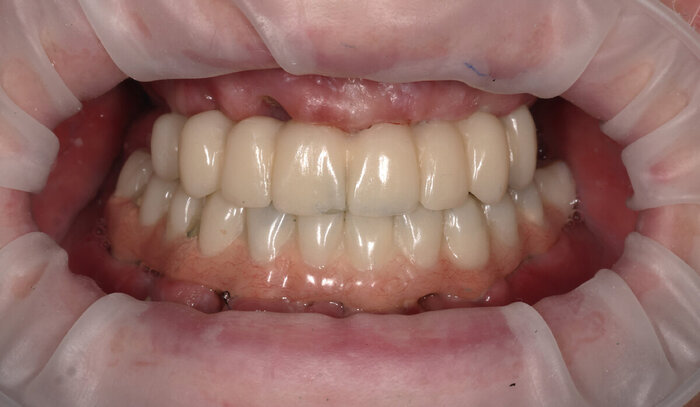

Временный адаптационный протез с опорой на 6 имплантов.

Временный адаптационный протез с опорой на 6 имплантов

Временный адаптационный протез с опорой на 6 имплантов. Нижняя челюсть.